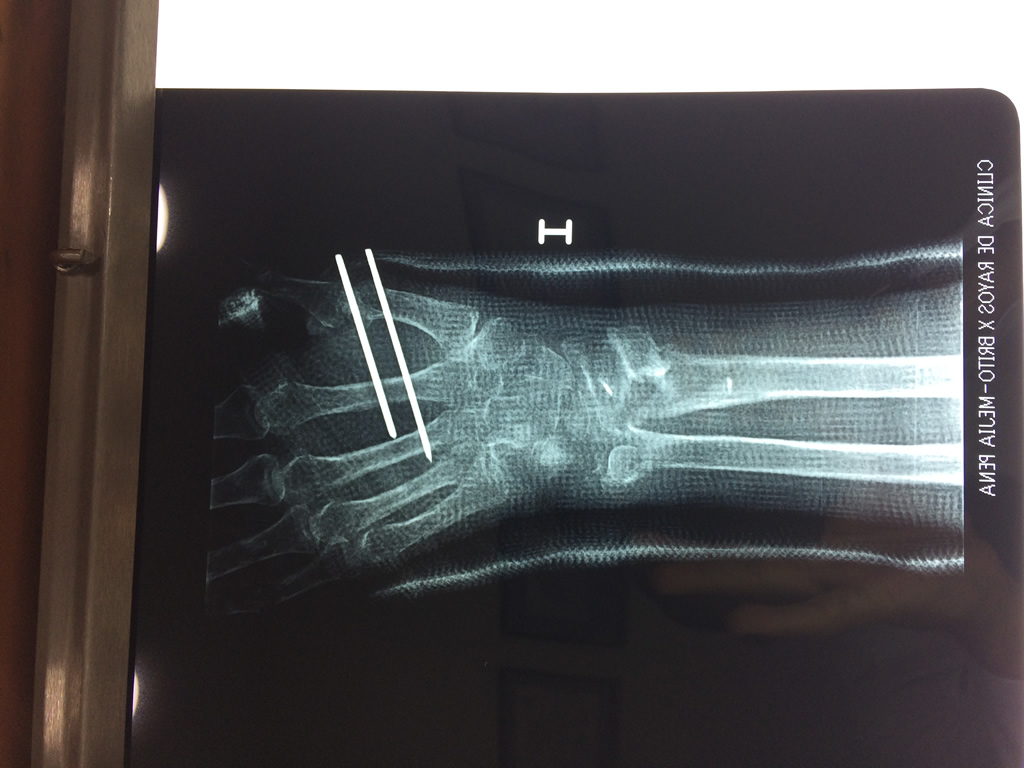

Calcaneo - Cirugías de Muñecas y Manos

Los procedimientos más comunes en cirugía de la mano son aquellos destinados a reparar traumatismos, incluyendo lesiones de tendones, nervios, vasos sanguíneos, y articulaciones; huesos fracturados; y quemaduras, cortes, y otros daños de la piel.